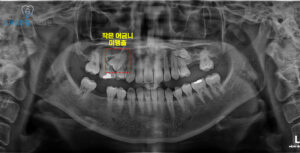

파노라마 사진을 촬영해 보니,

인접면으로 충치가 생겨

치아 뿌리 쪽까지

이어진 상태였는데요.

이 정도로 진행된 충치는

단순한 재치료로는

예후를 기대하기 어렵기 때문에,

장기적인 구강 건강을 위해

발치를 고려할 수밖에 없는

상황이었답니다.

인접한 작은 어금니가

잇몸 속에 묻혀 있는

미맹출 상태였기 때문이에요.

해당 치아는 위치상 교정을 통해

살려보는 방법도 검토했지만,

뿌리가 짧고 전반적인 예후가

좋지 않다고 판단되었어요.